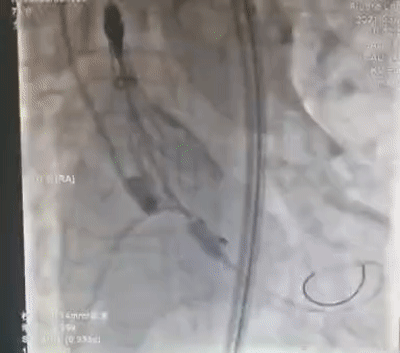

不开胸也能给心脏换“门”